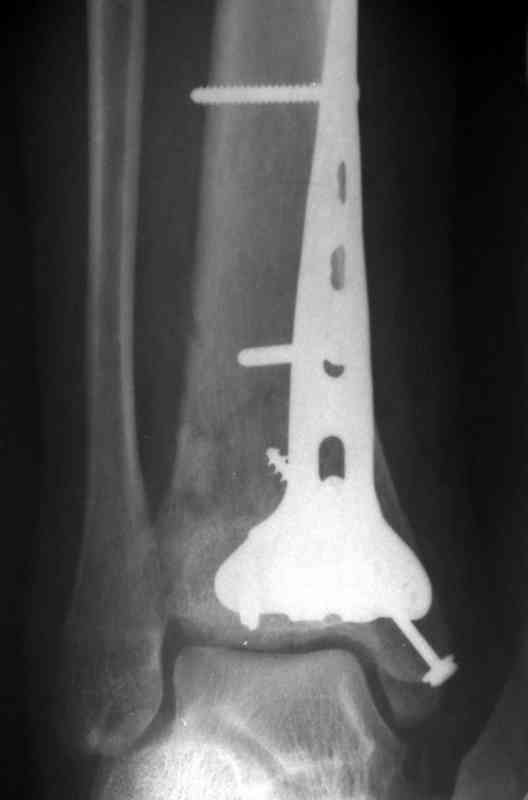

Это типичный перелом пилона, который надп лечить только открыто.Извини те что опоздал к обсуждению, но даже если вы уже оперировали больного по Илизарову это даже лучше.Посылаю картинки.

Посмотрим вроде прошло если понравится напишите расскажу как это сделать.По принципам АО кстати при поступлении сначала восстанавливают длину малоберцовой кости фиксируют пластиной 1/3 трубки потом накладывают аппарат наружной фиксации и через 7-10 дней открыто восстанавливают большеберцовую кость.С уважением Дрягин

На рентгенограммах типичный перелом пилона по типу С-3. есть опыт до 100 открытых опреаций у нас в клинике. 20 примерно в год. Принцип один -все внутрисуставные переломы нуждаются в открытой репозиции и внутренней стабильной фиксации. При поступлении КТ не надо, так как получается только нагромождение костей. Истинной картины нет. Главное восстановить длину малоберцовой кости - это ключ к успеху. При поступлении меньше всего надо думать о сосудистых расстройствах, т.к. сама операция и репозиция даже сначала частичная даёт улучшение сосудитых нарушений. Причём очень быстро. Операция в 2этапа. При поступлении доступ позади наружной лодыжки, причём обязательно. После этого репозиция малоберцовой кости и фиксация пластиной 1/3 трубки под винт 3,5. Дренаж и любой аппарат наружной фиксации. Затем после спадения отёка на 5-7-10 день аппрат снимается и дугообразный разрез спереди от медиальной лодыжки 10-12 см. Главной чтобы расстояние между 1 и вторым разрезом было не меньше 7-8 см. Тогда не будет некрозов лоскутов. Таранная кость используется как матрица на неё укладываются отломки и фиксируются пицами. Ренг-контроль. Отломки лежат все отдельно, но ничего не высыпется. При переломах С-3 всегда нужна костная пластика (из крыла). Фиксация пластиной лист клевера простой или LCP. Гипс не нужен. Дренаж до 48 часов. Операция длится 3-4 часа обязательно без жгута. Посылаю примерно такой же случай.

Посылаю результат лечения предыдущего больного через год.